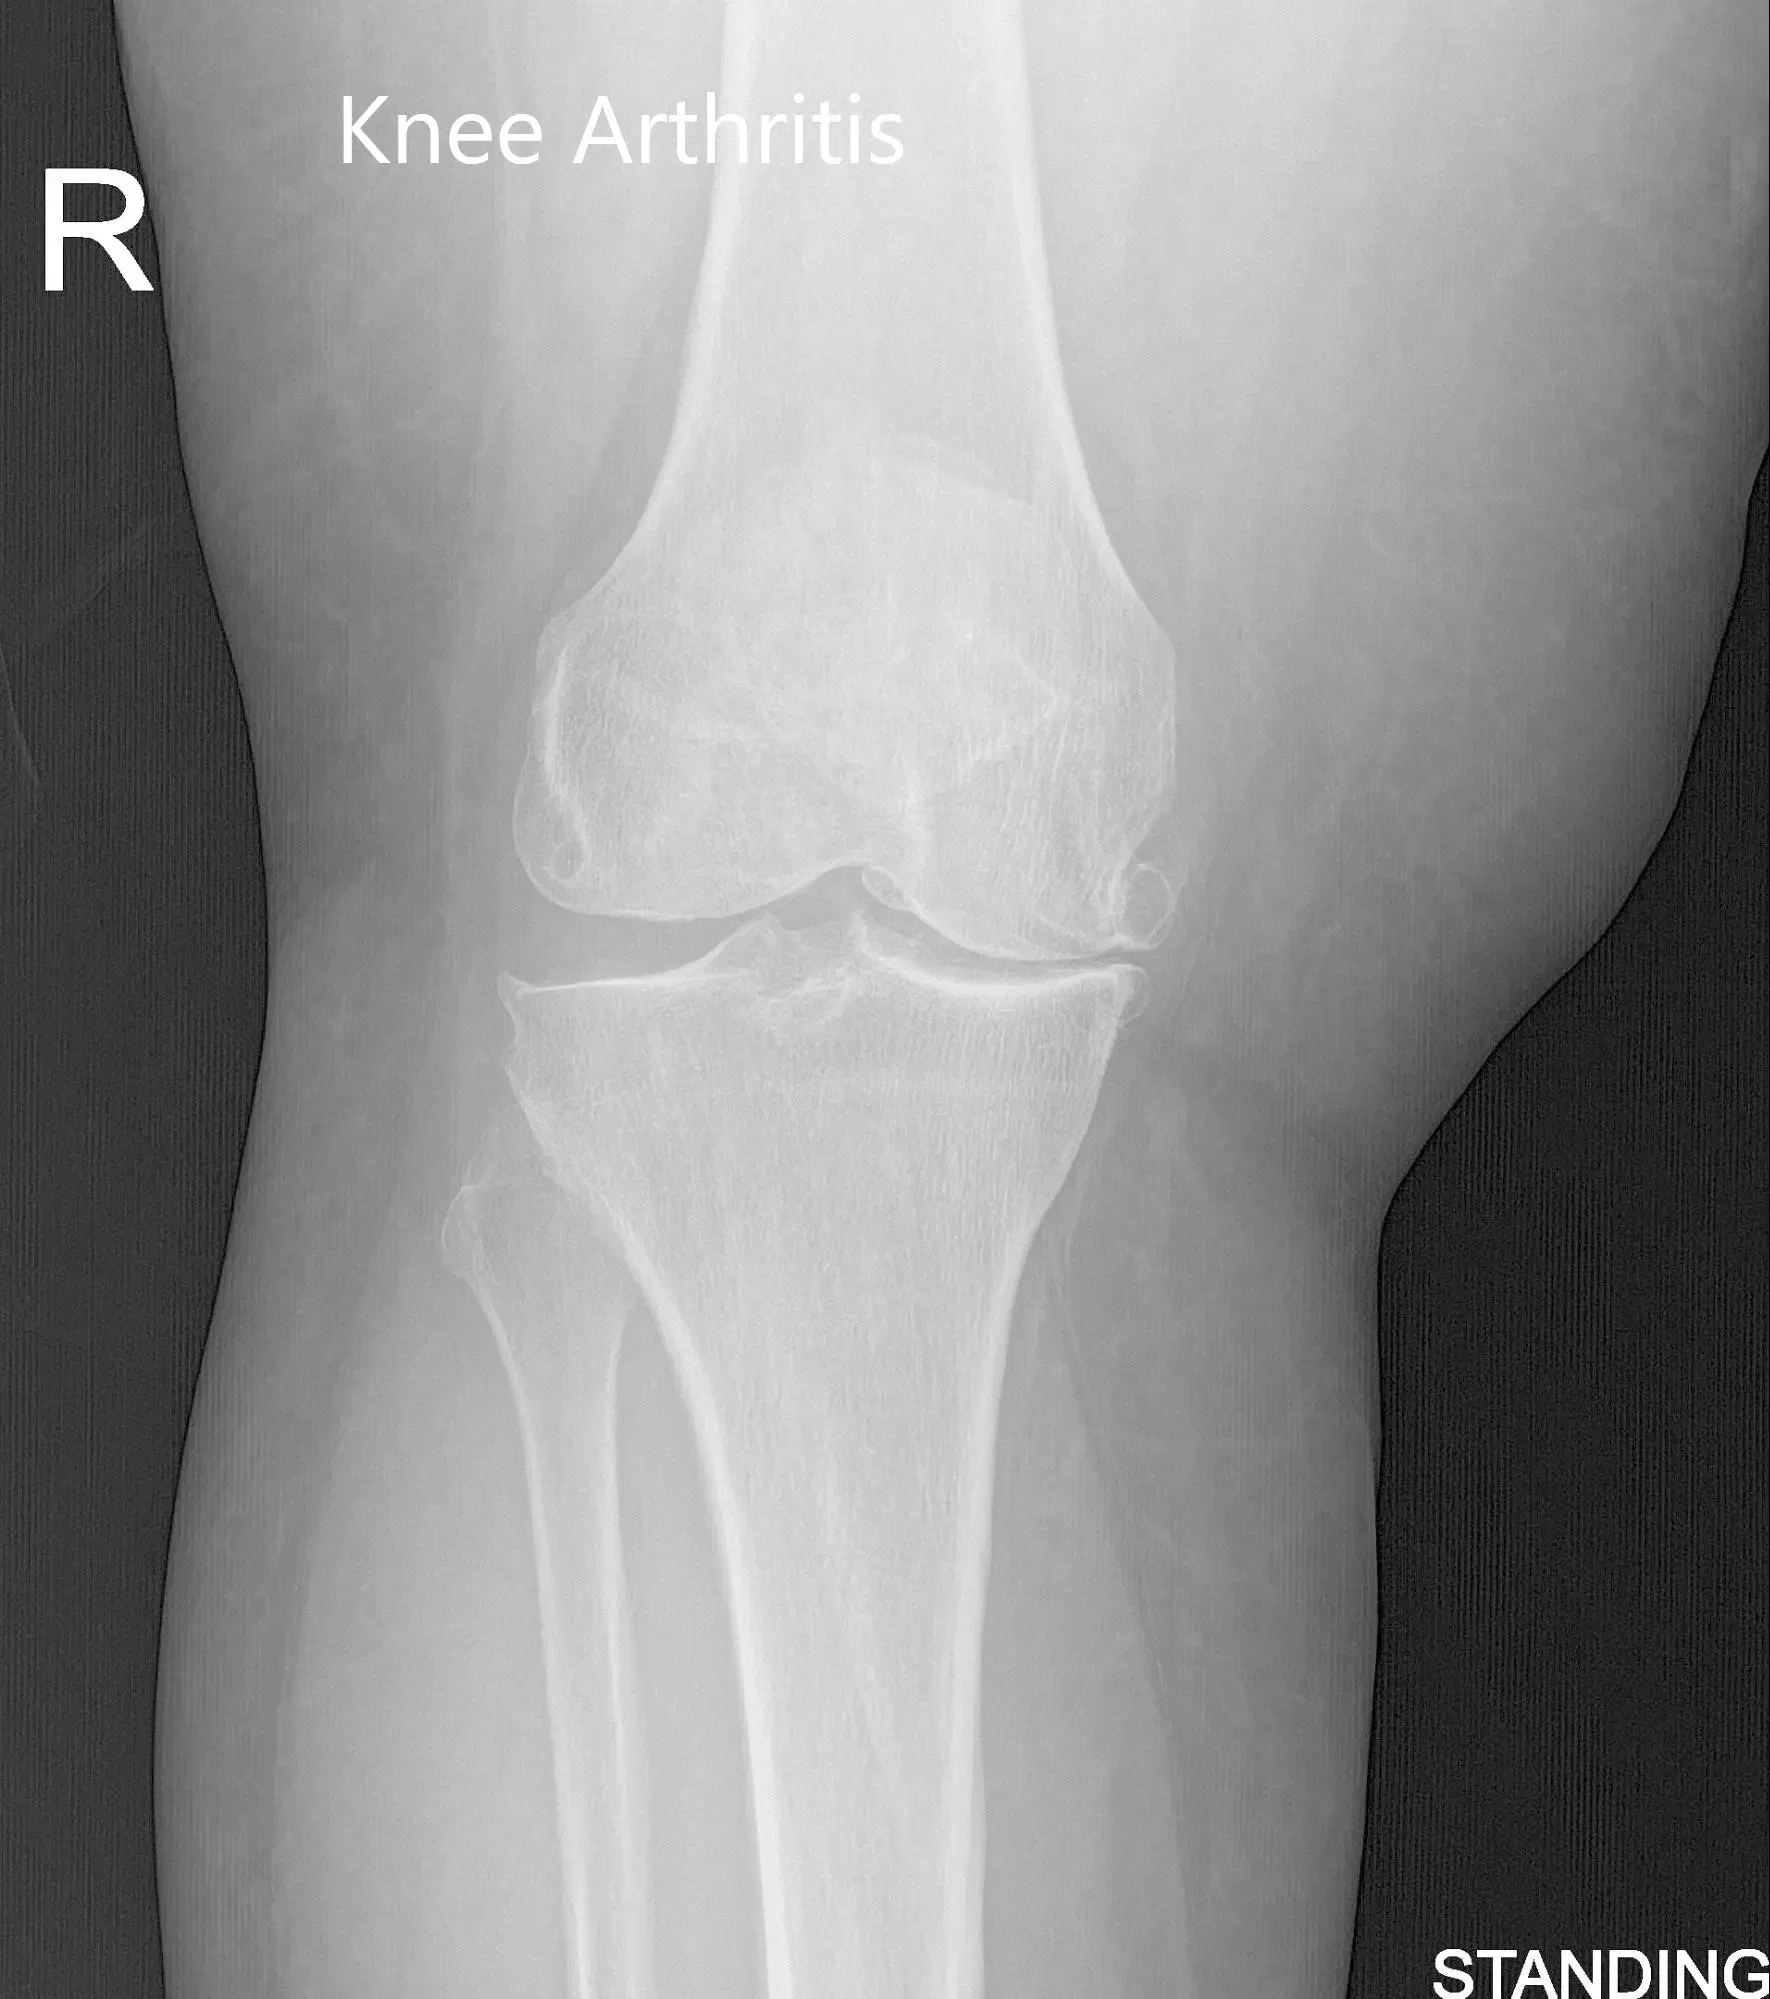

Vistas preoperatorias de la rodilla derecha con AP y radiografía lateral